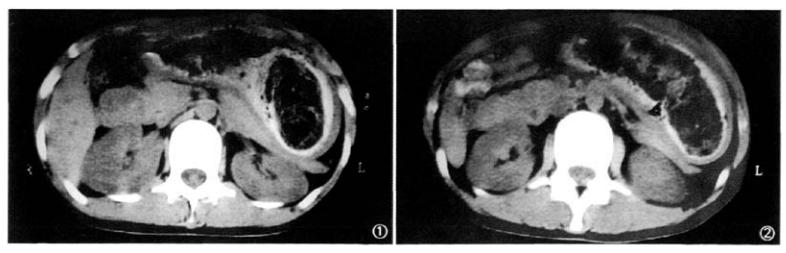

CT平扫,可见胃底及胃体内长团状混杂密度影。

平扫示胃底及胃体内长团状混杂密度影,边缘不光滑,与胃壁间见高密度造影剂,团块内部为低密度,CT值53Hu[6]。如何治疗?

[6]姚斯元,马玉超.CT诊断胃巨大毛发结石1例[J].中国医学影像学杂志,2008,16(4):319.DOI:10.3969/j.issn.1005-5185.2008.04.034.